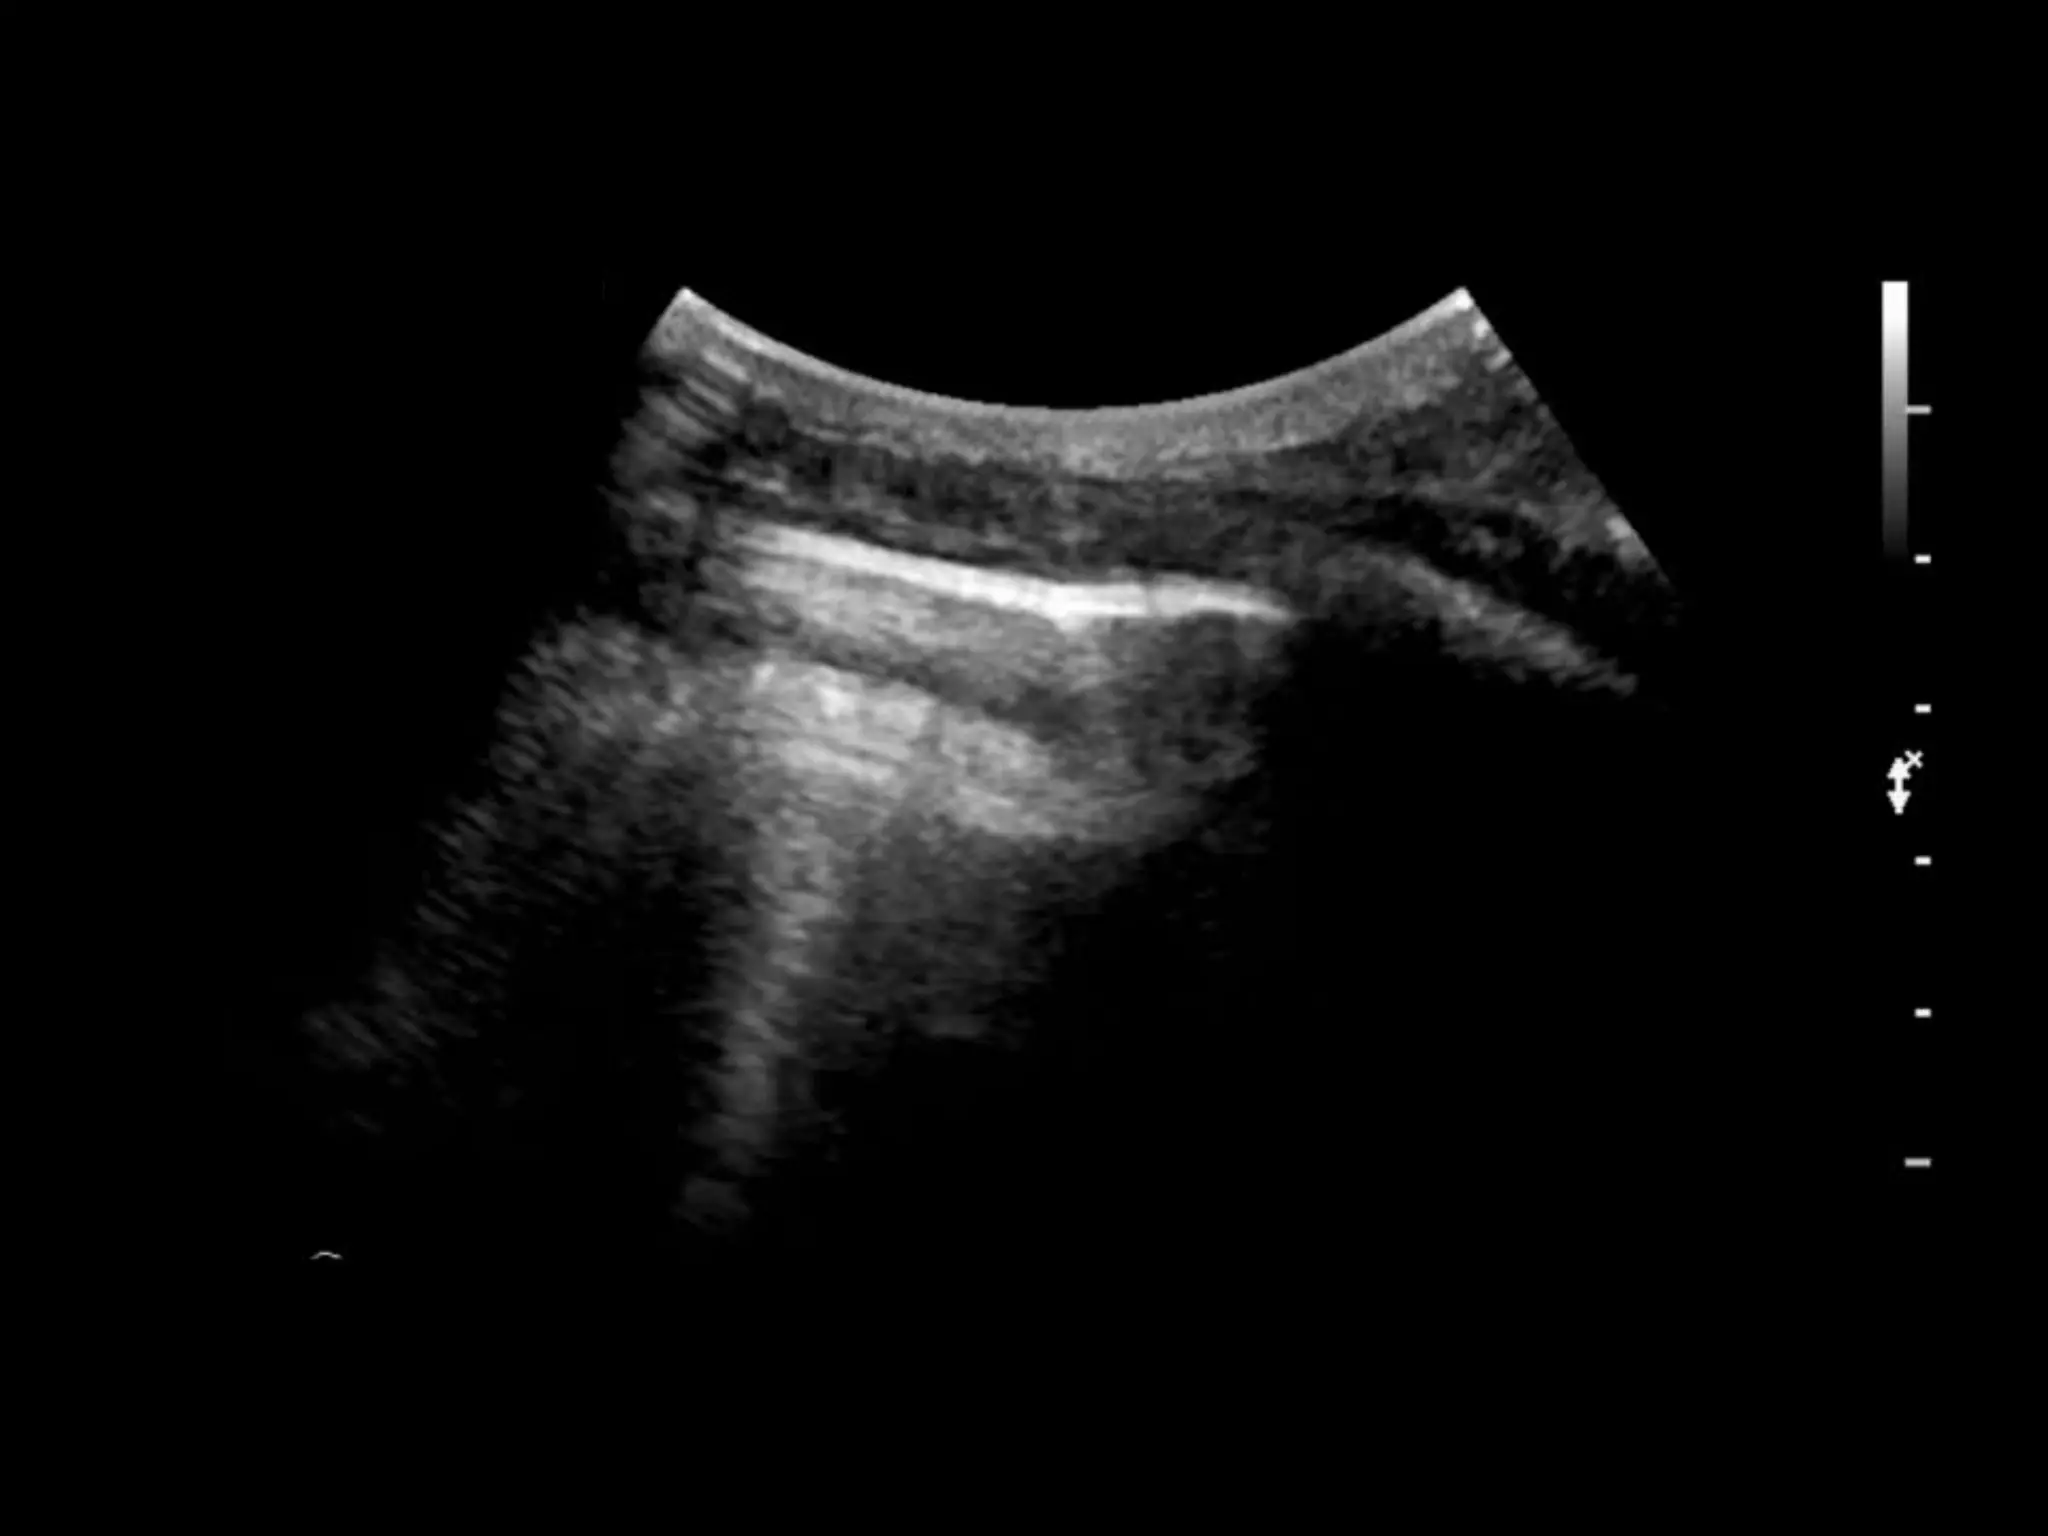

Case study 11

• Young woman

• Recent flight

• Increasing shortness of breath

• This is a rib, you are on the long axis, it may

look like a pneumothorax

• This is sliding the transducer off the rib onto a

pleural space

• Hydropneumothorax